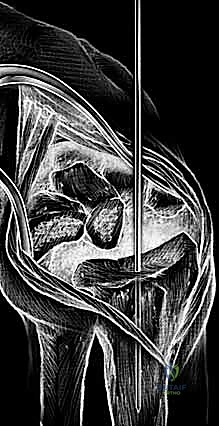

لفهم مدى دقة وبراعة عملية زراعة مفصل الرسغ، يجب أن نفهم أولاً طبيعة هذا المفصل. يتكون الرسغ من التقاء عظمي الساعد (الكعبرة والزند) مع ثماني عظام صغيرة تُعرف بعظام الرسغ (Carpal bones)، مرتبة في صفين. هذه العظام مغطاة بطبقة ناعمة من الغضروف المفصلي الذي يسمح بانزلاقها بسلاسة فوق بعضها البعض.

تحيط بهذه العظام شبكة معقدة من الأربطة القوية التي تحافظ على استقرارها، بالإضافة إلى الأوتار التي تمر عبر الرسغ لتشغيل الأصابع، والأعصاب الحساسة (مثل العصب الأوسط والعصب الزندي) والأوعية الدموية. أي تآكل في الغضروف يؤدي إلى احتكاك العظام ببعضها البعض، مما يولد ألماً شديداً والتهاباً مزمناً. الجراح الذي يقوم باستبدال هذا المفصل يجب أن يمتلك مهارة فائقة في الجراحة الميكروسكوبية وجراحة اليد لتجنب إتلاف هذه الهياكل الحيوية المحيطة.

3. الشق الجراحي والوصول للمفصل

يقوم الدكتور هطيف بعمل شق جراحي دقيق في الجزء الخلفي (الظهري) من الرسغ. يتم إبعاد الأوتار والأعصاب بحذر شديد باستخدام أدوات دقيقة لحمايتها من أي ضرر أثناء العملية.

4. إزالة العظام والغضاريف التالفة

باستخدام أدوات جراحية متخصصة، يتم إزالة الصف الأول من عظام الرسغ التالفة، بالإضافة إلى إزالة أطراف عظمة الكعبرة المتآكلة، لتهيئة المساحة لاستقبال المفصل الصناعي الجديد.